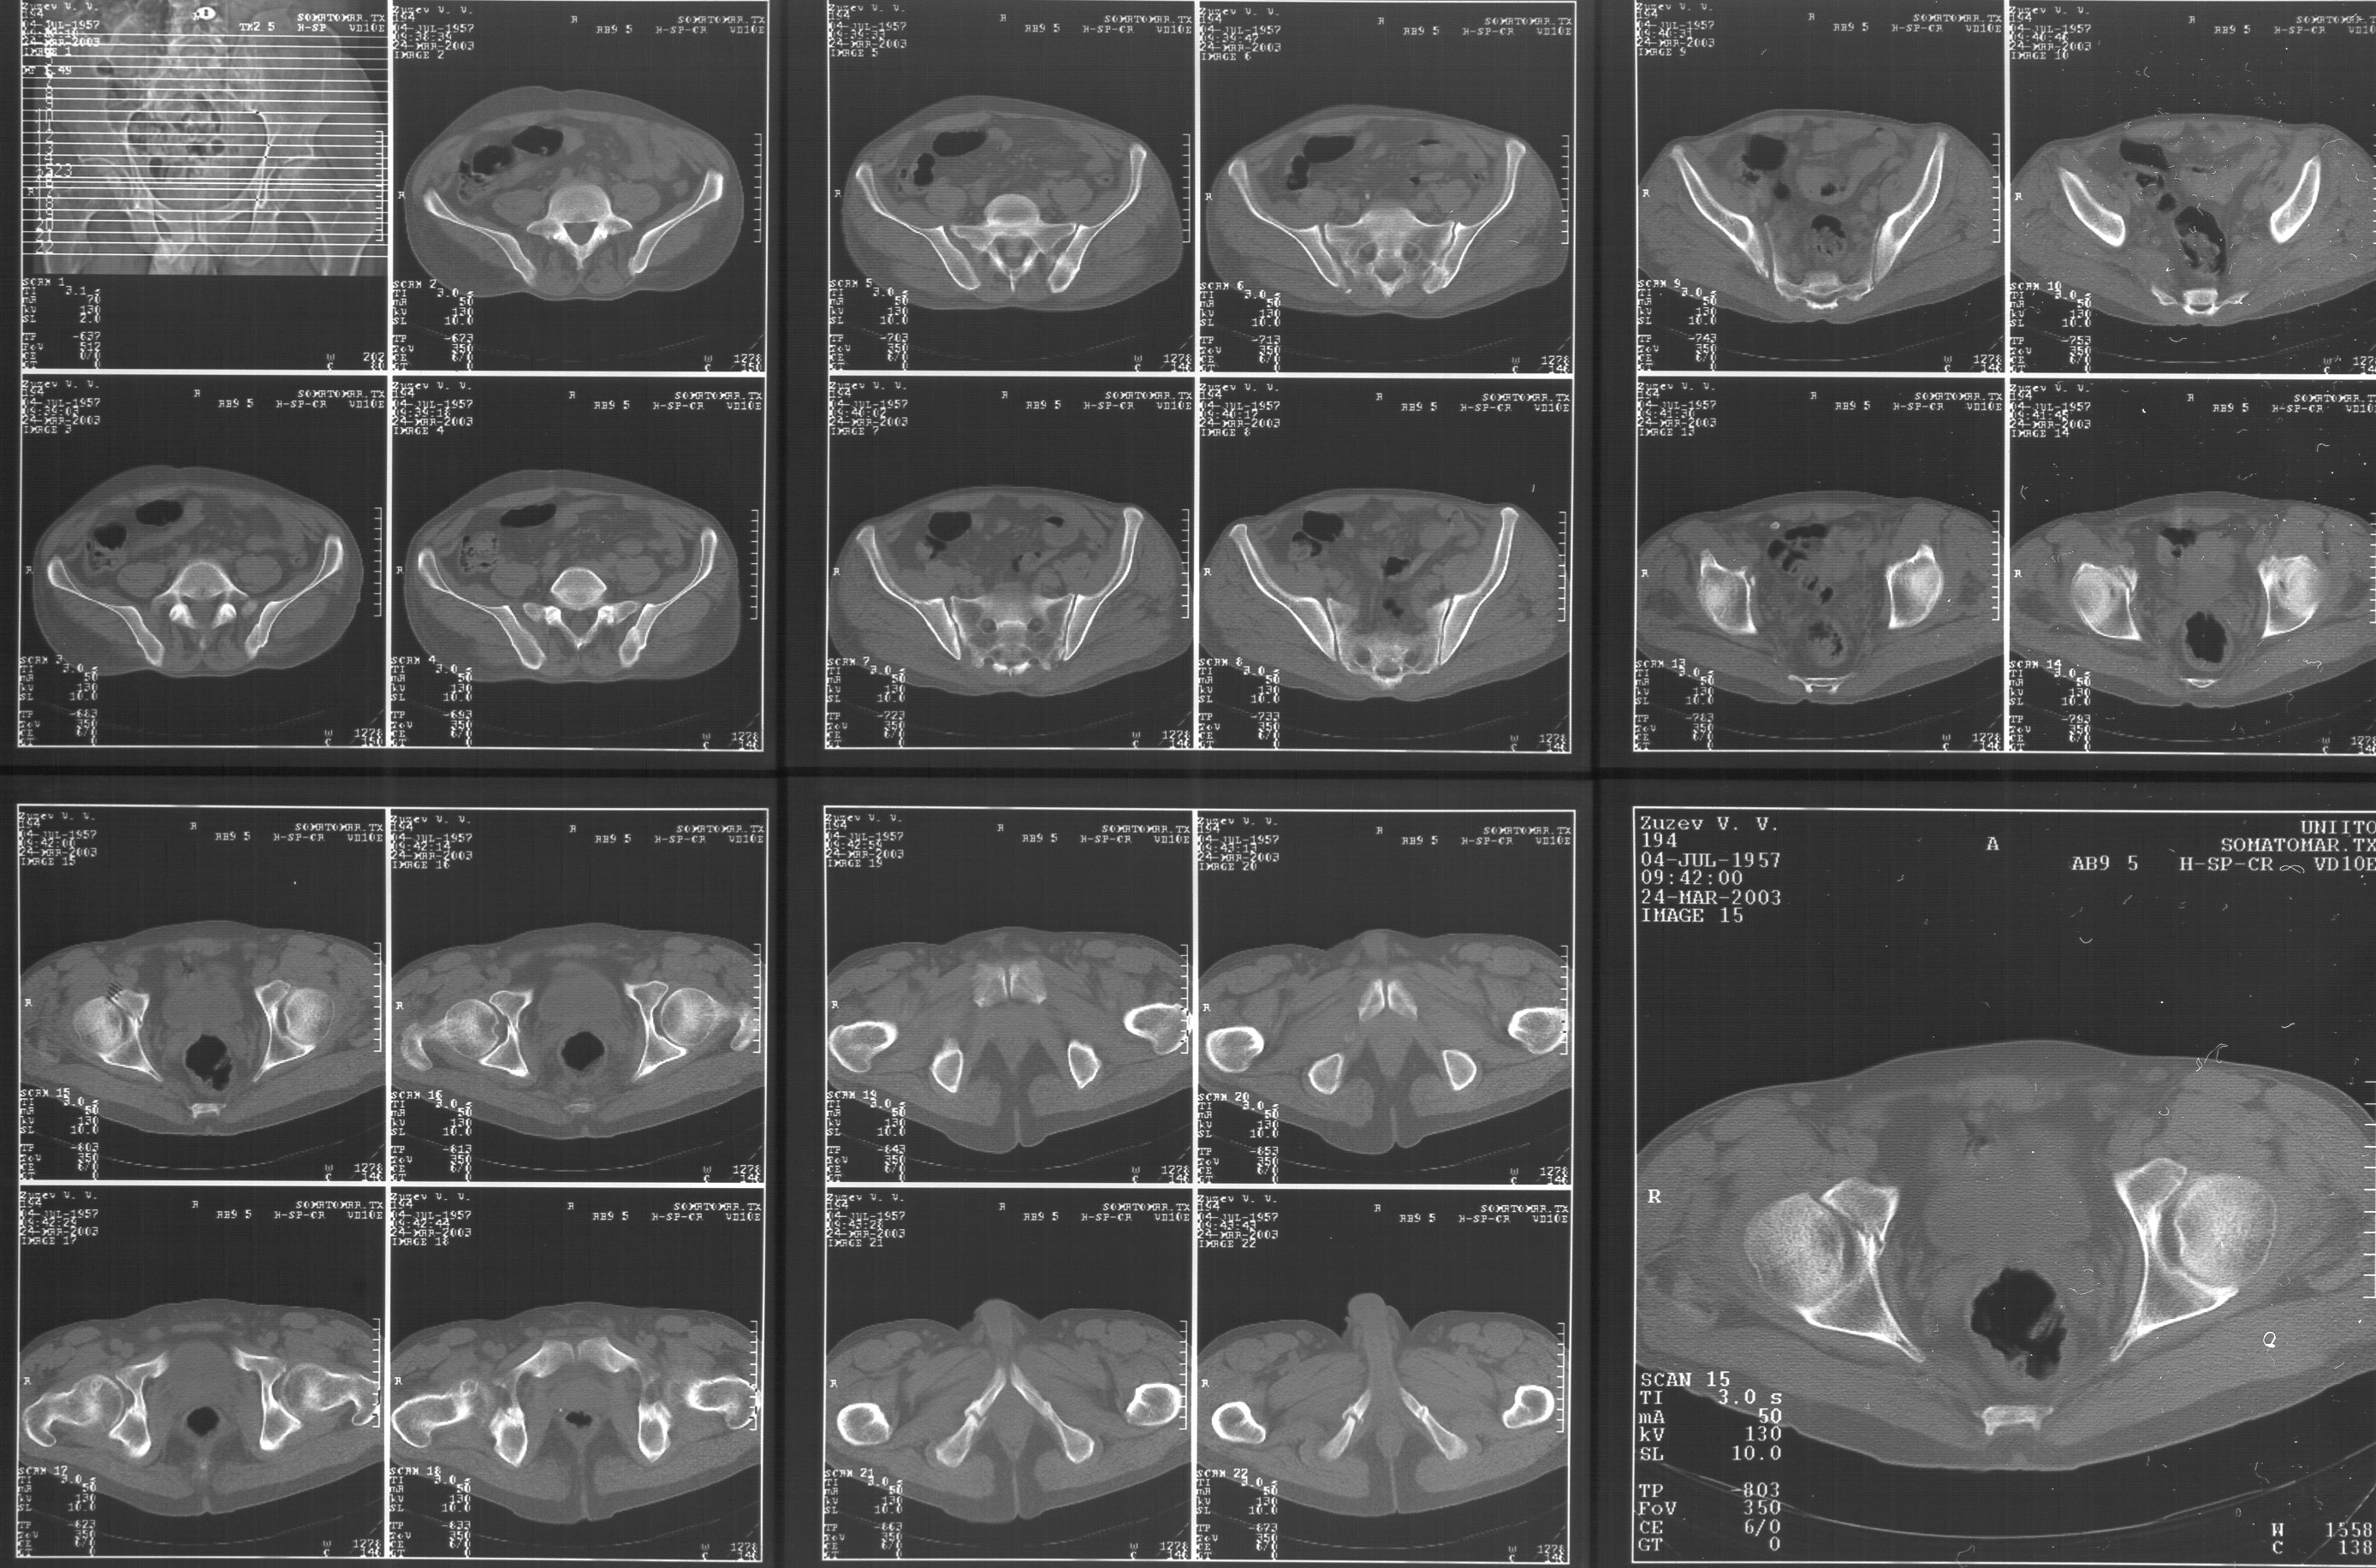

Прилагаю свежую КТ таза.

Картинки см. ниже, левая - с экранным разрешением, вторая - полноразмерная, ~900 кб.

КТ в экранном разрешении

Полноразмрная картинка, около 900 кб

Based on the CT images you provided, he appears to have a nonunion of the the right ischium, which would explain his symptoms. General principles of treatment of hypertrophic (which this appears to be) nonunions suggest rigid fixation, but I'm not sure what the best approach would be. Could get a lag screw across the fracture through a Kocher-Langenbeck approach or plate osteosynthesis through direct ischial approach, but perhaps Chip, Adam or someone with more pelvic fracture experience could enlighten us all.

I think this is just a pelvic ring disruption that has gone on to a non-union. The arrow is pointing to the inferior ramus non-union, and

the sup ramus is a high "root" fracture, right near the pecten. The sup ramus fracture enters the tab - you could call it an acetabular

fracture - but down here in Dallas we treat these acutely as stable pelvic ring injuries. The fracture in the anterior portion of the

acetabulum is so low it doesn't seem to cause much trouble.

His R sacroiliac joint is opened anteriorly a little bit - the "unreduced posterior lesion" Alex mentioned in his first post. My earlier post about plating, bone grafting, etc., is all wrong.

What you have is a pelvic fracture that hasn't healed after 4 months or so, with a minimal deformity.

I think what I would offer the guy is a percutaneous iliosacral screw to stabilize and improve the SI joint alignment, coupled with a perc anterior column screw to stabilize the high ramus fx. These screws aren't easy to place, and have a host of potential problems and complications. But, I think they would work.

Как Вы сами видели на томограммах, грубых деструктивных явлений крестцово-подвздошного сочленения не определяется( маркировка правая -левая сторона не видна), определяется сравнительно незначительное расширение суставной щели с одной стороны и не более того.

Виноват, первый раз не обратил внимания на возможность полноформатного просмотра томограмм. В этой связи -дополнения к своему первому комментарию: сросшийся перелом вертлужной впадины справа, L5-S1 спондилоартроз, расширение суставной щели крестцово-подвдзошного сочленения справа может компрометировать его стабильность и вызывать локальные боли, но вряд ли это может давать двусторонние проявления в нижних конечностях. Все-таки миелограмма или ЯМР желательно иметь, чтобы определиться в тактике.